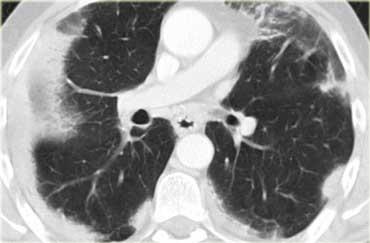

Tạo hang trong lao phổi

Phim X-quang ngực bên trái cho thấy các vùng đông đặc khoang khí dạng nốt lan tỏa.

HRCT chứng minh nhiều nốt phân bố quanh phế quản, một phần hợp lưu, và một ổ tạo hang ở phổi phải, gợi ý mạnh cho chẩn đoán lao phổi.

Các bệnh lý khác trong chẩn đoán phân biệt bao gồm u hạt Wegener hoặc ác tính (cả hai đều không có hình ảnh “cành cây nảy chồi”).